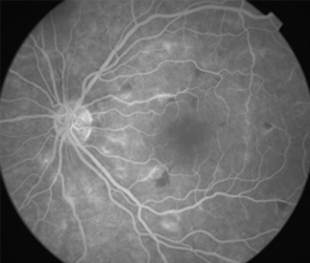

Angiografía OI

2 meses: disminución de manchas algodonosas y hemorragias con mejoría de circulación

- Angiografía: teñido arterial, escape capilar, más tardíamente, no perfusion arteriolar y venular con teñido de las paredes vasculares y dilatación venosa.